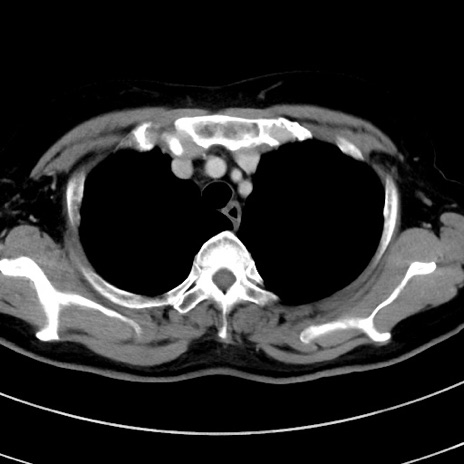

症例9(横断像)

【症例】 60歳代女性

【主訴】むかつき、みぞおちの痛み

【現病歴】3日前よりむかつきがあり、食事がとれない。

【既往歴】糖尿病

【身体所見】発熱なし、心窩部圧痛軽度あるも、腹膜刺激症状なし。

【データ】WBC 7400、CRP 1.92